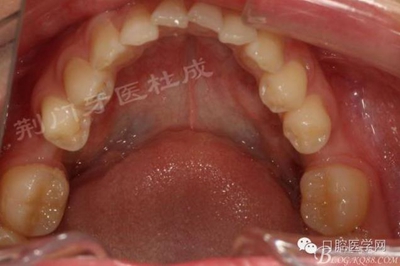

術(shù)前口內(nèi)照片:

檢查:16齲壞穿髓,探(-)叩(+++),無松動,36 46 缺失,37 47 近中傾斜嚴(yán)重,44畸形中央尖牙體變色,叩(+),溫度測試無反應(yīng) ,18 28 38 48 萌出牙體偏頰